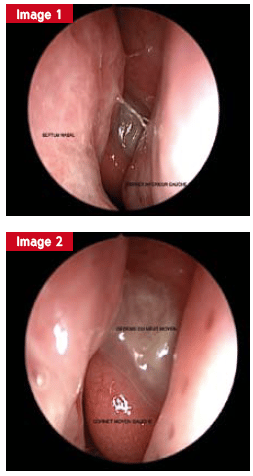

Endoscopie de la cavité nasale

L’exploration de la cavité nasale reste l’étape de base pour toute pathologie rhino-sinusienne. Les avancées technologiques (optique, imagerie, rhinomanométrie, étude de la clairance mucociliaire, etc.) ont transformé l’examen, désormais plus précis et informatif.

L’endoscopie nasale, incontournable pour l’ORL, fait suite à un examen minutieux et à une rhinoscopie. Elle aide à distinguer un problème de structure d’un trouble fonctionnel. Dans les pathologies fonctionnelles, elle révèle les signes d’inflammation (œdème, pus, croûtes) et leur localisation.

Cette procédure se réalise avec une fibre optique souple ou une optique rigide, et l’endoscopie vidéo numérique gagne du terrain. L’examen, sous anesthésie locale associée à un vasoconstricteur, optimise le confort et la visibilité.

Le nasofibroscope, flexible et fin, ne permet pas d’intervention associée lors de l’examen. L’optique rigide, par contre, offre une image de meilleure qualité et laisse une main libre pour aspirer ou prélever au besoin.

L’endoscopie permet de scruter l’état de la muqueuse, la présence d’œdèmes, de croûtes, ou de sécrétions (séreuses, purulentes, sanglantes). Chaque cavité nasale est explorée avec rigueur : cloison, cornets, voûte, récessus, méats. Il est parfois nécessaire de repousser délicatement le cornet moyen pour accéder au méat moyen, lieu de drainage principal de certains sinus.

L’examen se complète par l’exploration du nasopharynx et des trompes auditives, dont le dysfonctionnement peut expliquer certains troubles, notamment chez les plongeurs.

La figure illustre un cas d’obstruction nasale unilatérale persistante, liée à un gonflement muriforme visible en endoscopie, révélant un papillome inversé. L’IRM met en évidence l’aspect spécifique de la lésion. Un polype antrochoanal, quant à lui, se manifeste par une obstruction nasale chronique et une rhinorrhée persistante, nécessitant une exérèse complète pour éviter les récidives.